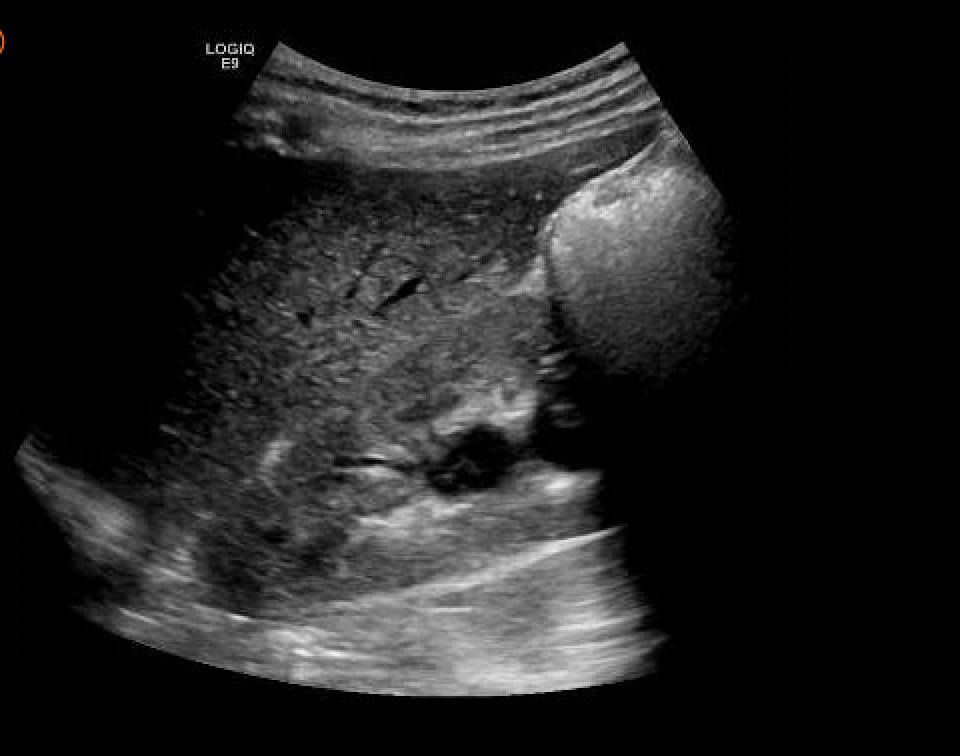

Hallazgos ecográficos

Juicio clínico: Hidronefrosis moderada por compresion uterina (embarazo).

Seguimiento: Evolución favorable, con desaparicion del dolor a la semana. Se realizó, nueva ecografía clínica en su centro de salud, confirmando la normalidad de la via urinaria (por movimientos fetales).

La hidronefrosis en el embarazo, suele aparecer hasta en un 90%, sin embargo solo un pequeño porcentaje presenta clínica (3%). Aparece en la segunda mitad de la gestación, siendo las causas extrinsecas las más habituales (compresión por aumento de las vena ovaricas y/o uterino). En la actualidad, sigue siendo la ecografía el mejor metodo para su diagnóstico por su inocuidad. En la mayoría de los casos, solo precisa tratamiento sintomático, hidratación y medidas posturales maternos (decubito lateral sobre el lado contrario al del riñón dilatado con intención de disminuir la compresión por el utero).